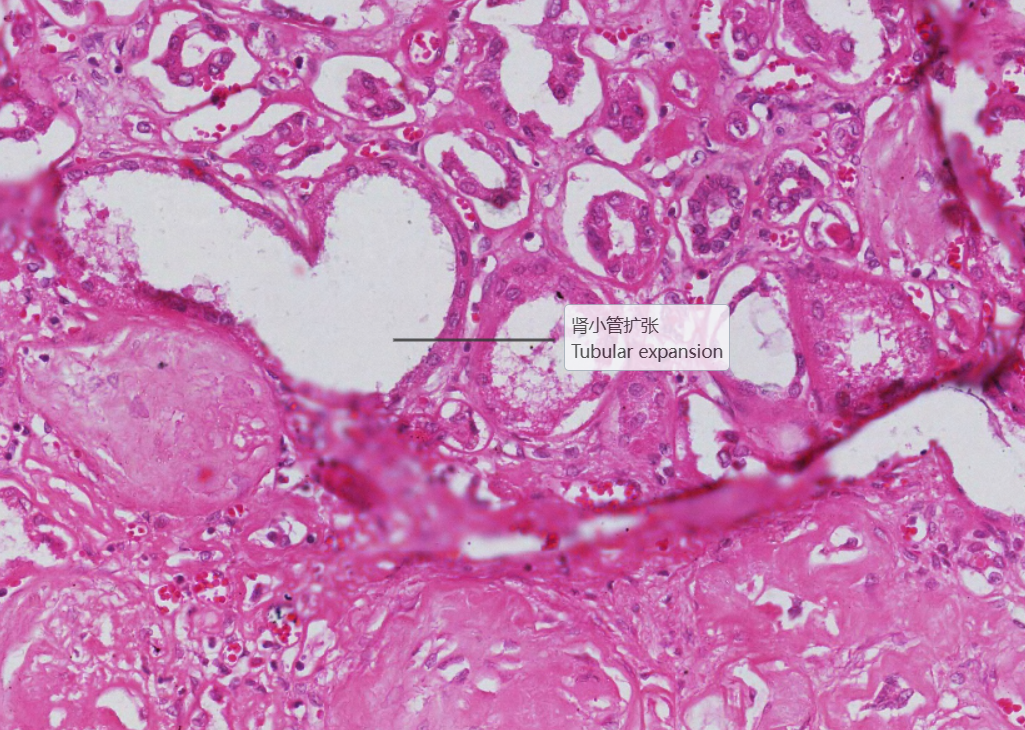

糖尿病肾病:1.大部分肾小球系膜区大量基质增多,较多形成结节状扩大,少数细胞靠结节边缘排列, 形成典型的K-W结节。部分节段有系膜细胞轻度增生, 基膜增厚。2.少数小球伴有球囊壁纤维化。 少部分肾小球硬化(玻璃样小体)。3.肾小管较多灶性萎缩,部分肾小管扩张,管腔内有蛋白管型。4.间质广泛纤维化,伴大量炎症细胞浸润(淋巴细胞、浆细胞)。许多肾小球入球细动脉壁增厚玻变, 间质肌性小动脉内膜增厚纤维化。

4.肾小管扩张